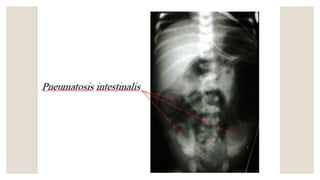

◦ 1. Plain abdominal x-rays :

◦ Pneumatosis intestinalis (air in the bowel wall) is diagnostic;

◦ Portal venous gas is a sign of severe disease, and

◦ Pneumoperitoneum indicates a perforation.